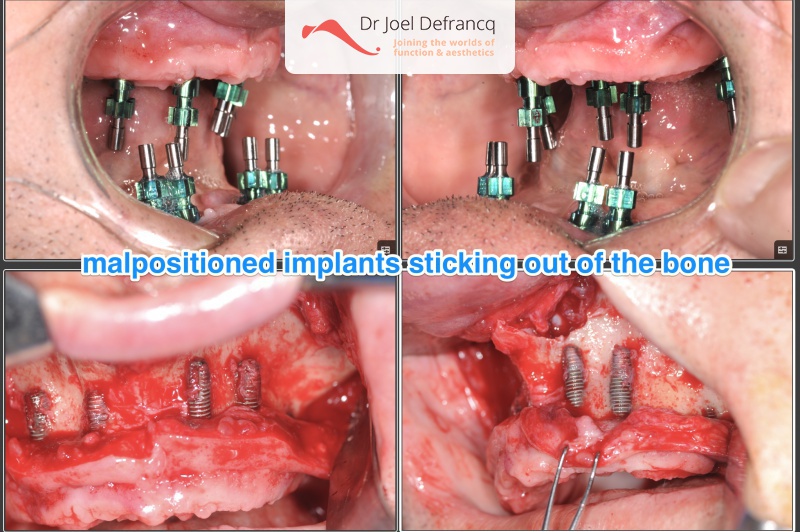

Behandeling tandheelkundige implantaten

- Vaste tanden op implantaten (bovenkaak)

- Vaste tanden op implantaten (onderkaak)